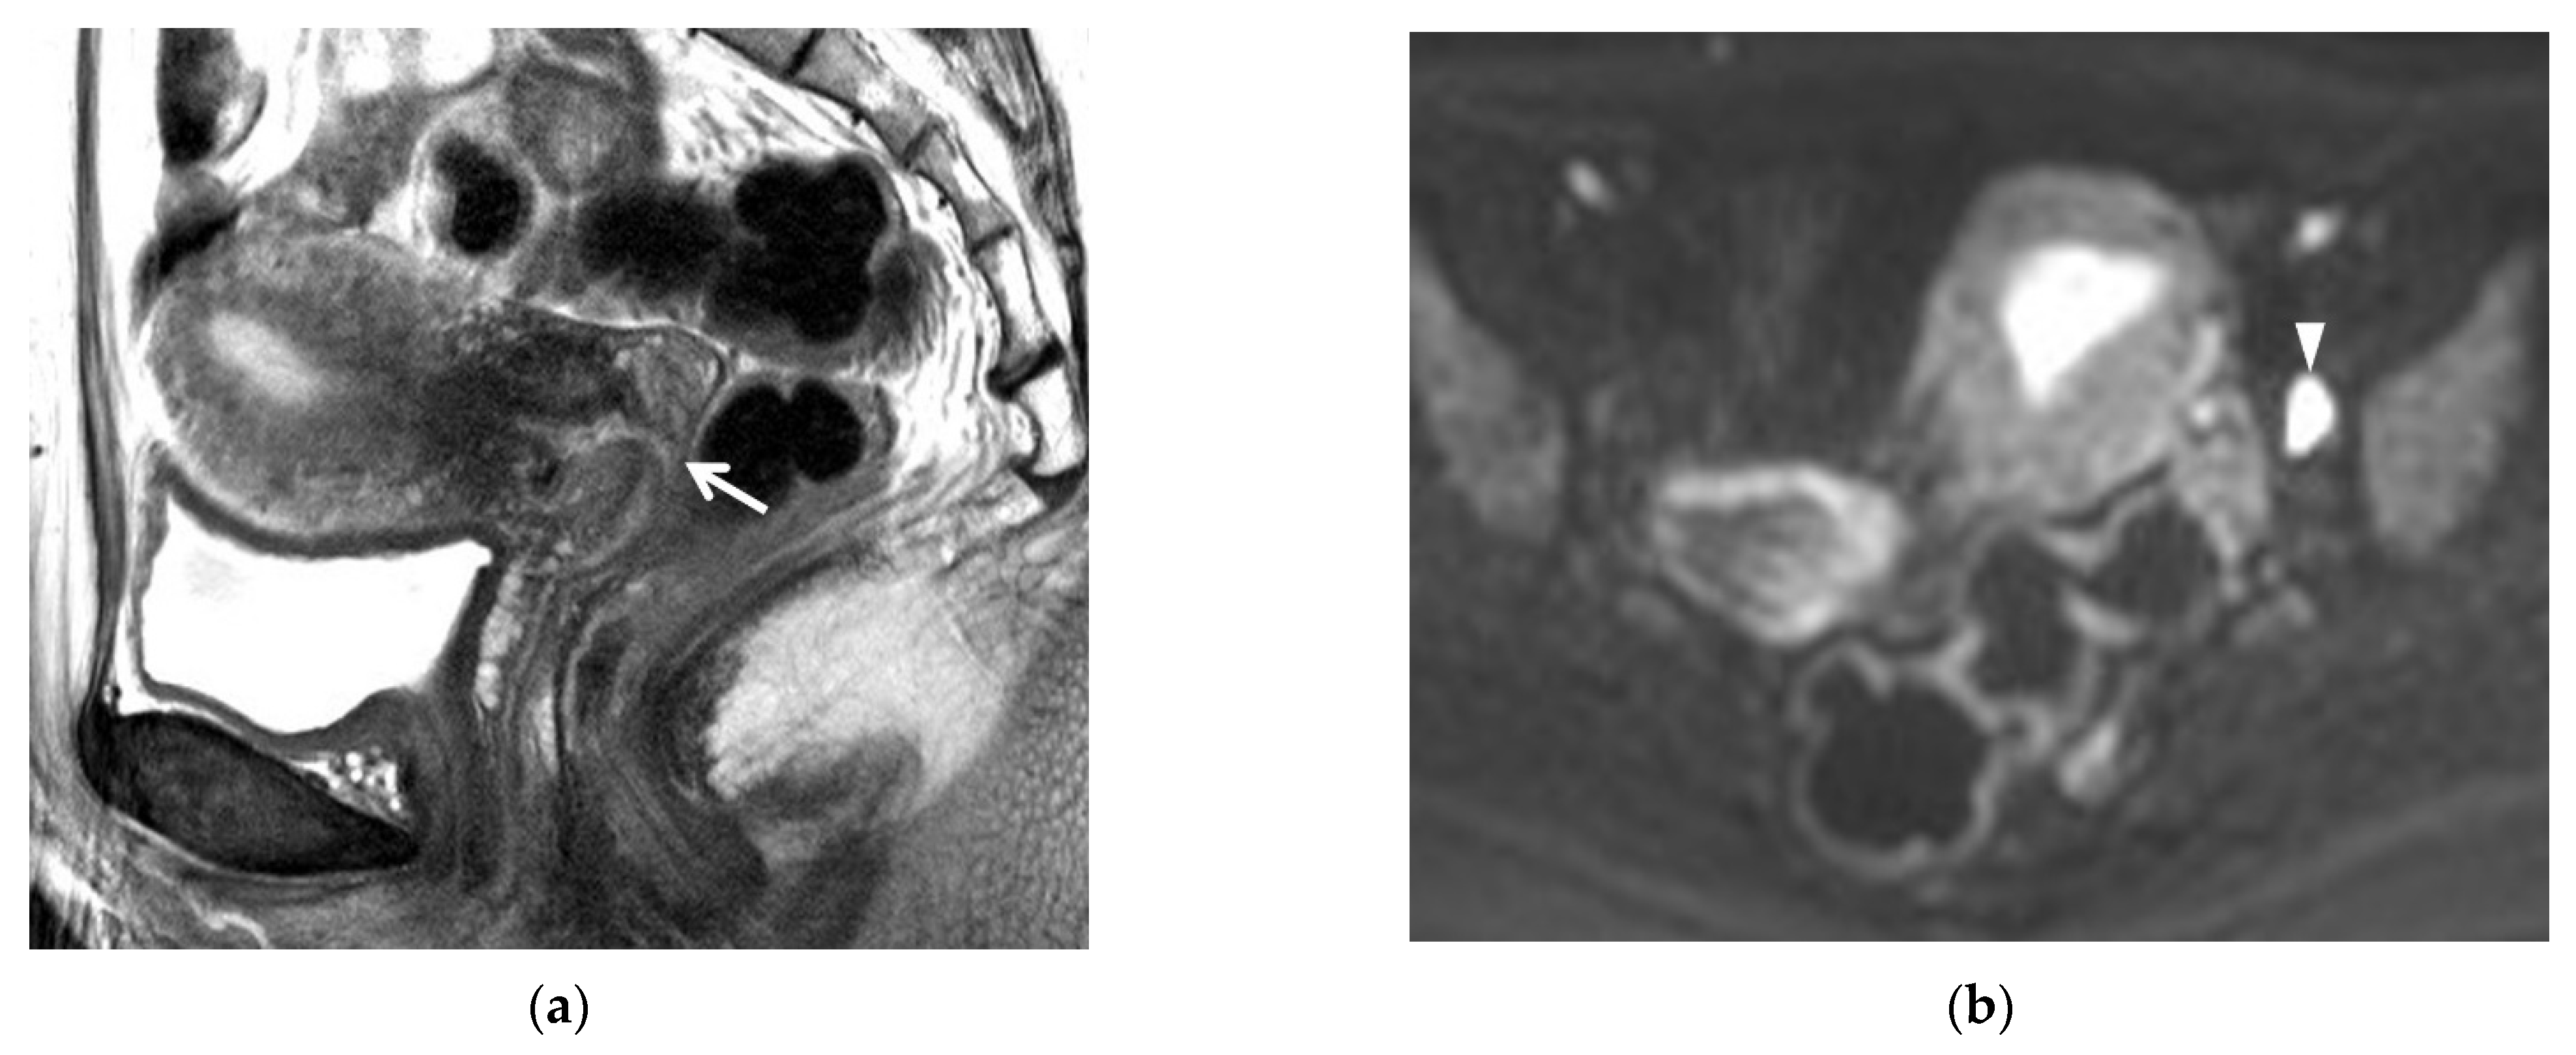

3.3. DWI Findings

4. Post-Conization MRI